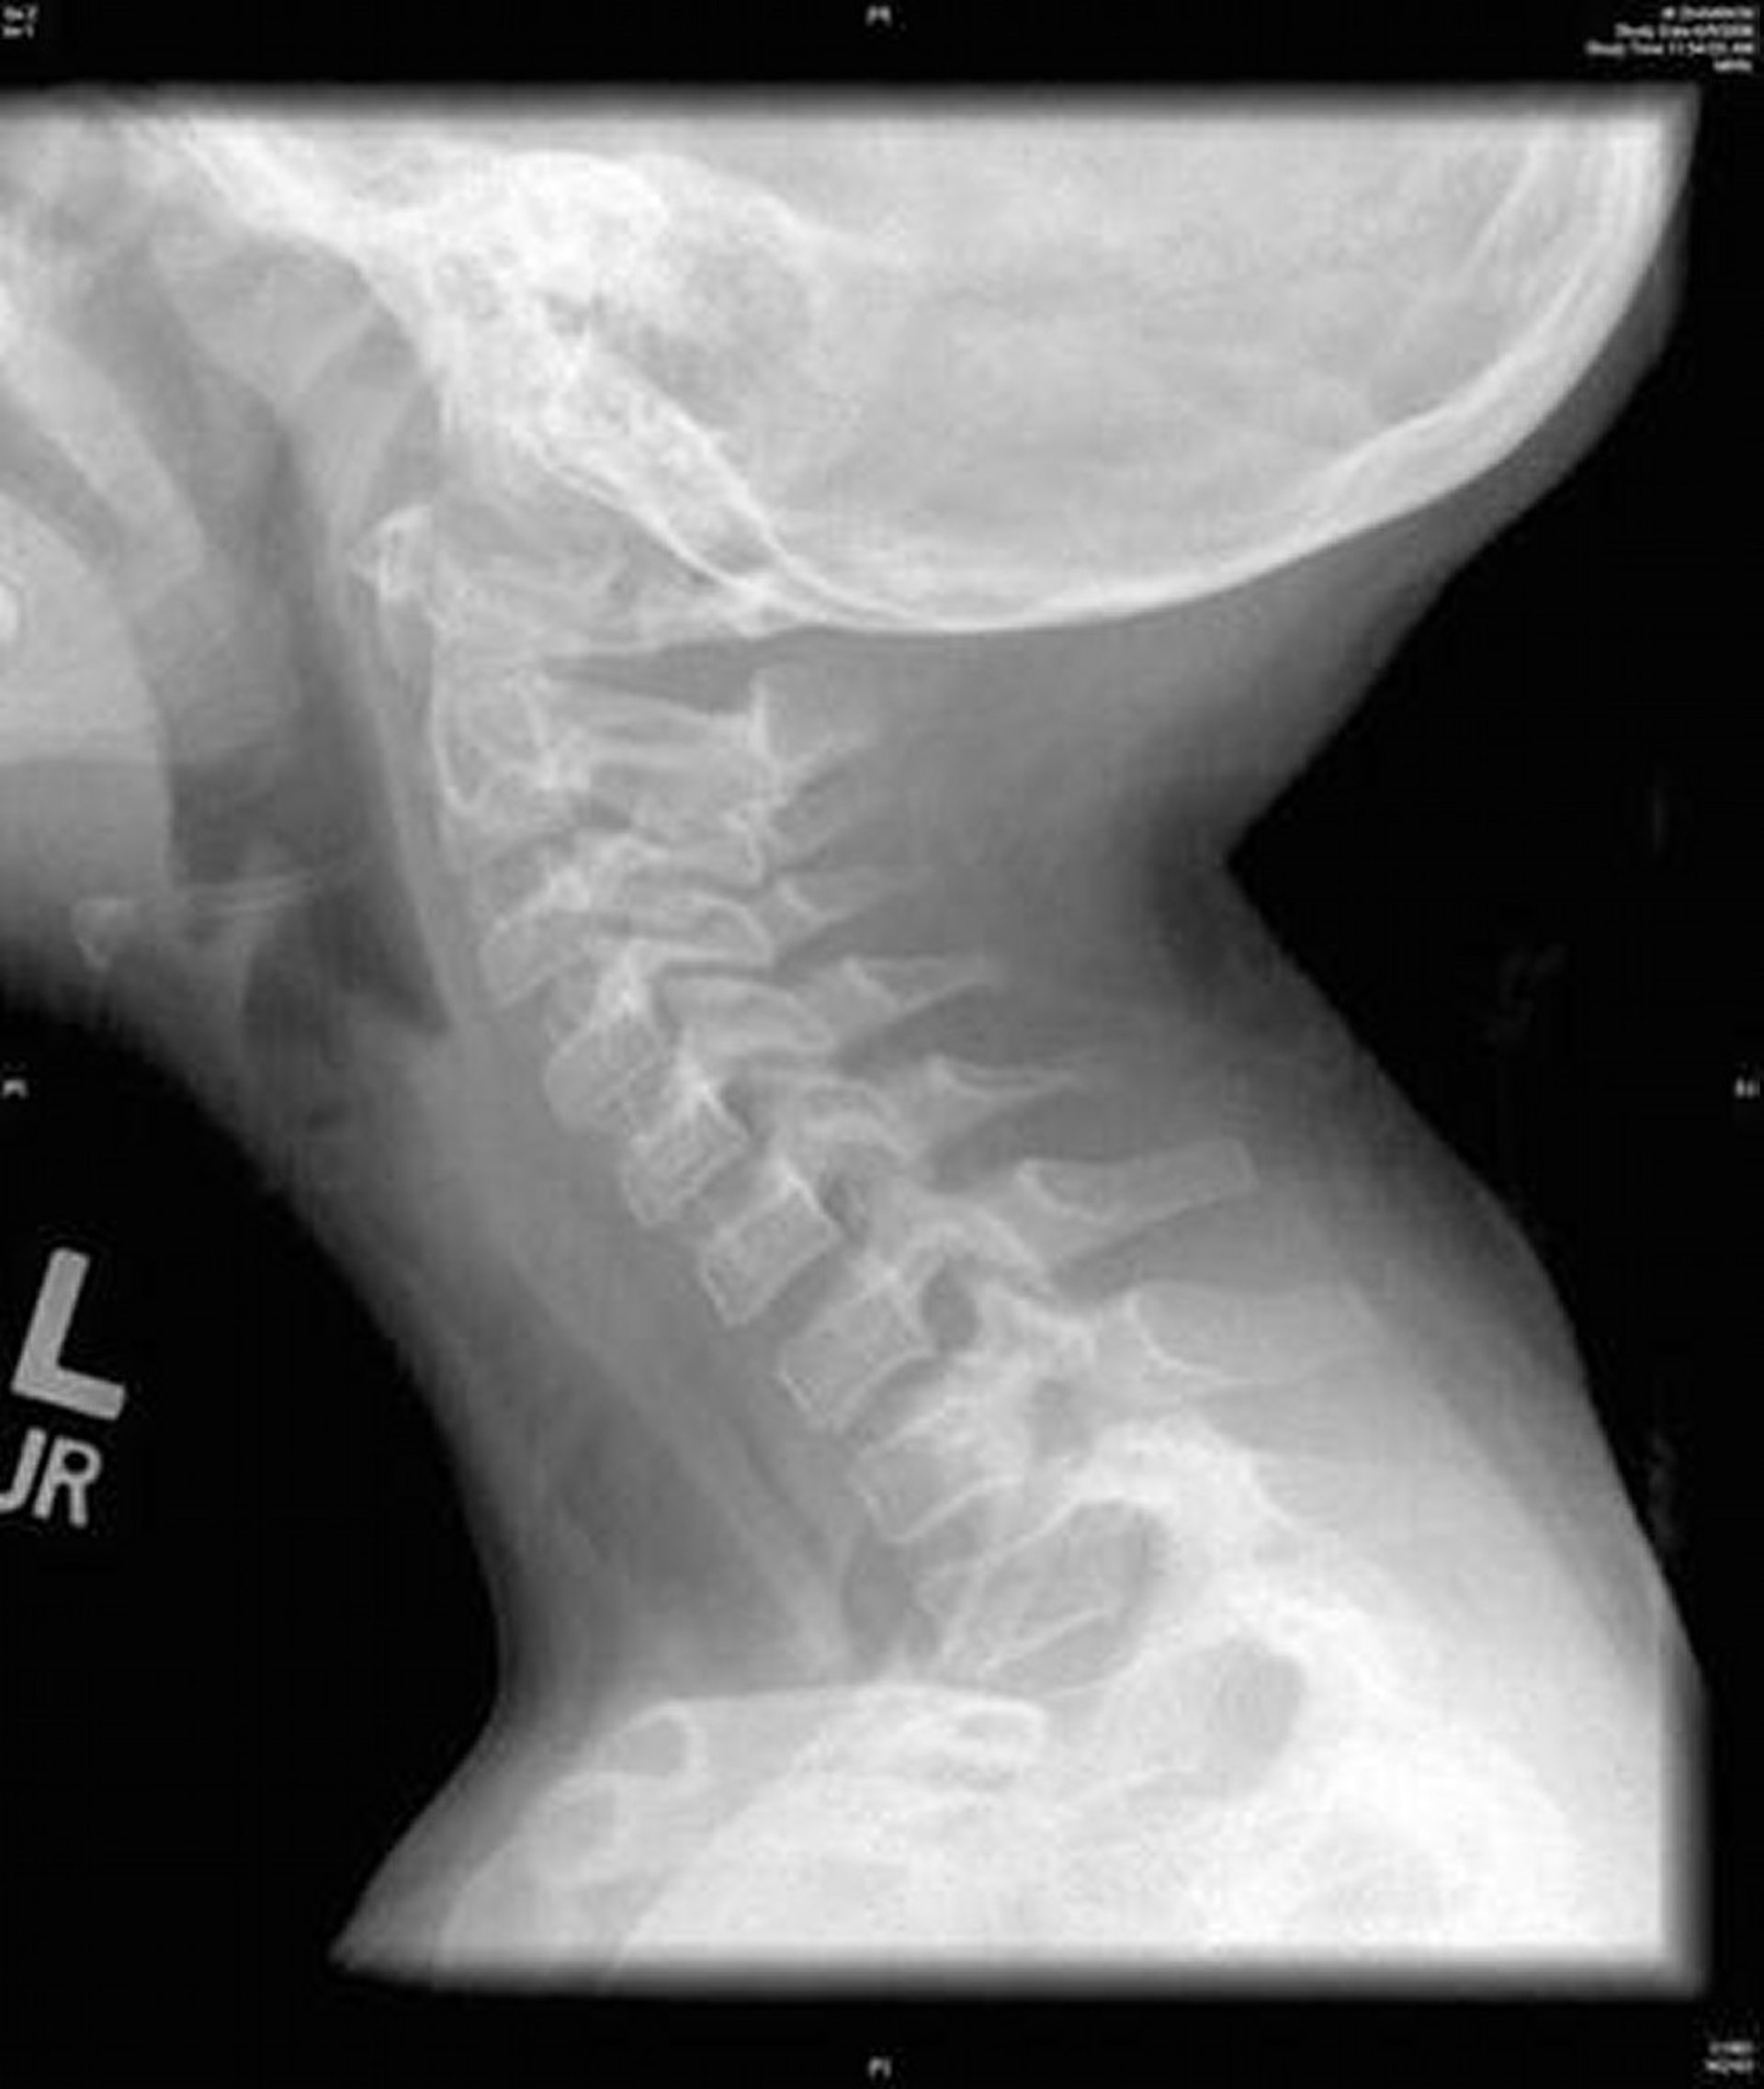

Bacterial Tracheitis (Radiograph)

This image shows a lateral radiograph of the neck that shows diffuse irregularity of the trachea characteristic of bacterial tracheitis.